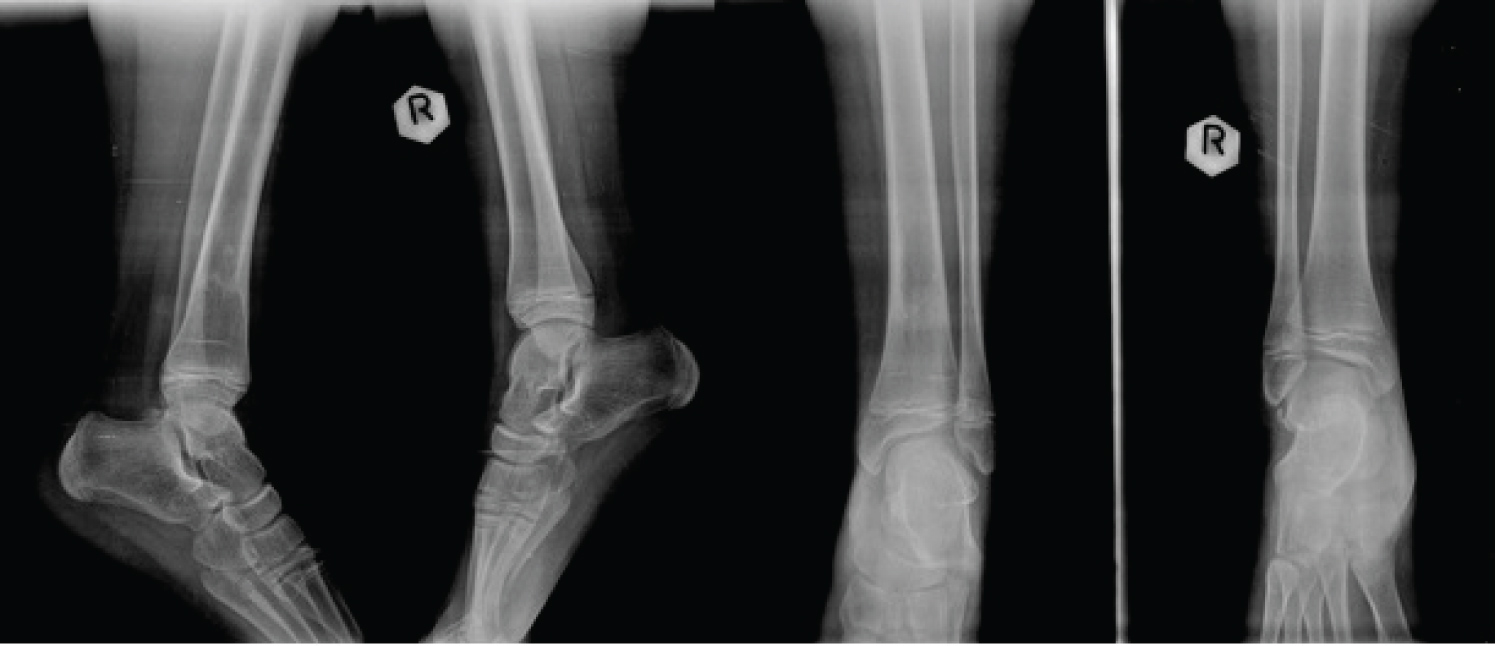

AP and lateral radiographs revealed a fracture of the distal tibial metaphysis with no significant displacement neither in the frontal nor in the sagittal plane. There was a limited recurvatum of 5 degrees with no varus/valgus deformity comparing to the other limb. There was also a concomitant fibular fracture (Figure 1). No osseous lesions were detected in the joints cranially or caudally to the fracture.

Figure 1: Comparative AP and lateral radiographs at presentation showing the barely displaced fractures of distal tibia and distal fibula metaphysis. View Figure 1